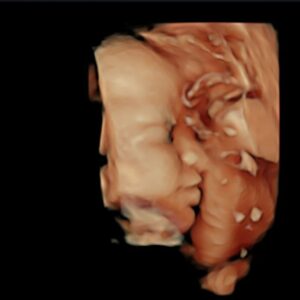

| Profile Photos | |

| https://instagram.com/chantelliu | Most Liked Instagram Photos of Chantel Liu |

View Full List of Most Liked Photos of Chantel Liu | |